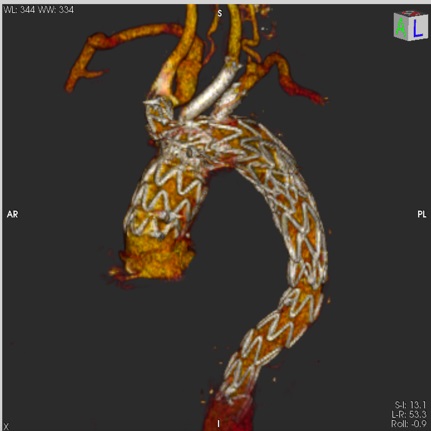

Operacja odbyła się bez powikłań. Zarówno kontrolna arteriografia, jak i angio-TK po zabiegu wykazały wyłączenie z układu krążenia rozwarstwienia w obrębie łuku aorty oraz prawidłowy przepływ krwi w tętnicach domózgowych.

Pionierska operacja stwarza możliwość w pełni wewnątrznaczyniowego, jednoetapowego zaopatrywania rozwarstwień i tętniaków łuku aorty, a jej małoinwazyjność oraz brak konieczności wykorzystania krążenia pozaustrojowego niewątpliwie dają szansę na skrócenie czasu hospitalizacji i okresu rehabilitacji pooperacyjnej.

Należy również podkreślić, że szybka dostępność stentgraftu off the shelf, w porównaniu do systemów fenestrowanych lub systemów z odgałęzieniami typ „custom-made”, których produkcja trwa nawet kilka tygodni, umożliwia wykonywanie zabiegów w trybie pilnym.